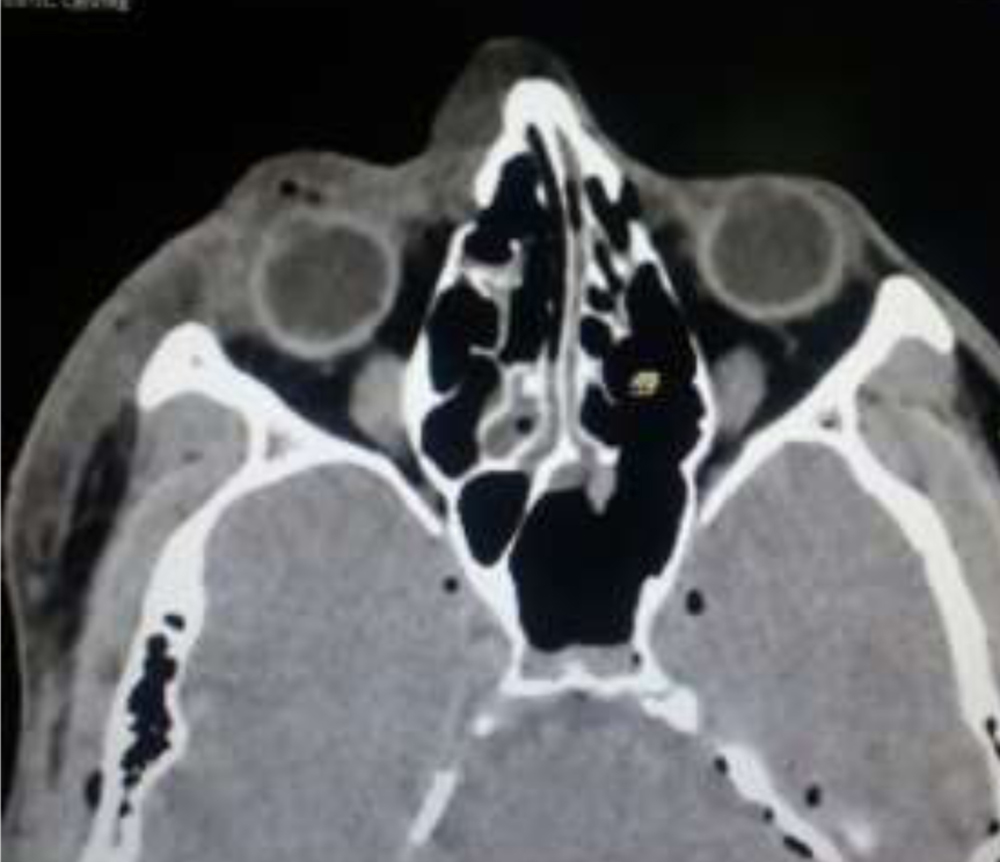

Ultrasound bscanrevealed  no signs of globe peforation .CT brain showed swollen soft tissues around the orbital and maxillary region.(Figure 3).Patient was started on treatment as per the standard protocol for thermal eye injury including broad spectrum  iv and  topical antibiotics, topical steroids and cycloplegics.Within 48 hours, development of eschared tight eyelids with  necrosis spreading to adjacent soft tissues around maxillary region  and collapsed anterior chamber were noted.(Figure 2).Repeat bscan was done and chorioretinaldetatchment was ruled out. Immediate exploration of eyeball with debridment of eyelids and surrounding soft tissue was planned .Intraoperatively  debrided tissue was noted to be dusky ,with necrosis of all four recti muscles.There was no signs of globe perforation  and hence the reason for  collapsed AC was concluded  to be due to ciliary shutdown.Debridement continued until bleeding and normal tissue planes were appreciated.AC was reformed and  lateral canthotomy was performed .

Figure 3 CT Brain axial view showing swelling of periorbital soft tissues(OD).